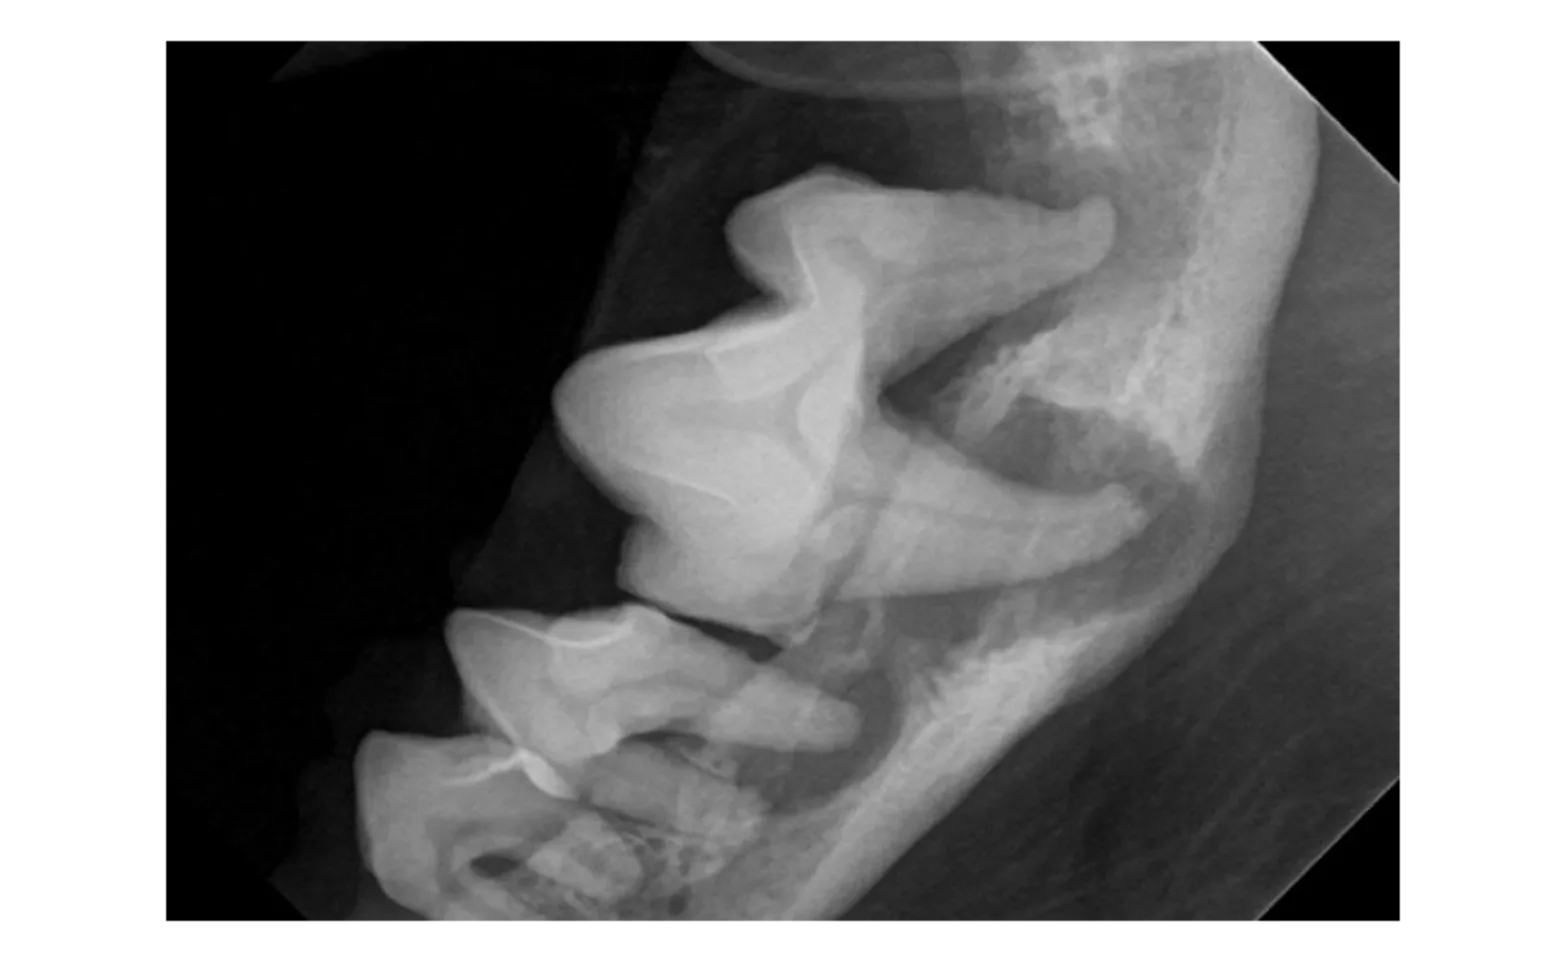

Full Mouth Digital Dental Radiographs –

More than half the tooth is under the gum line where we can’t see. Studies show that more than half of the patients receiving a dental cleaning WITHOUT dental radiographs will be sent home with untreated, painful conditions.